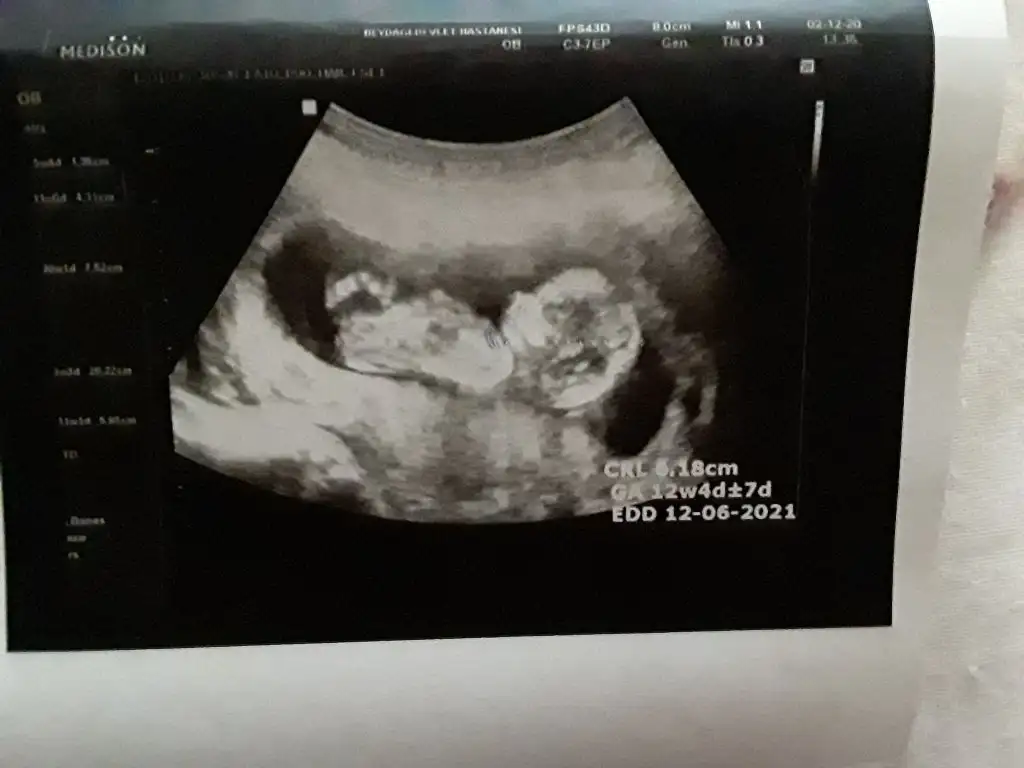

Erkeğe benziyor goruntusuKizlar 12 haftalik bebegimin cinsiyet tahmini yapar misiniz cok merak ediyorum :) Eki Görüntüle 2685687